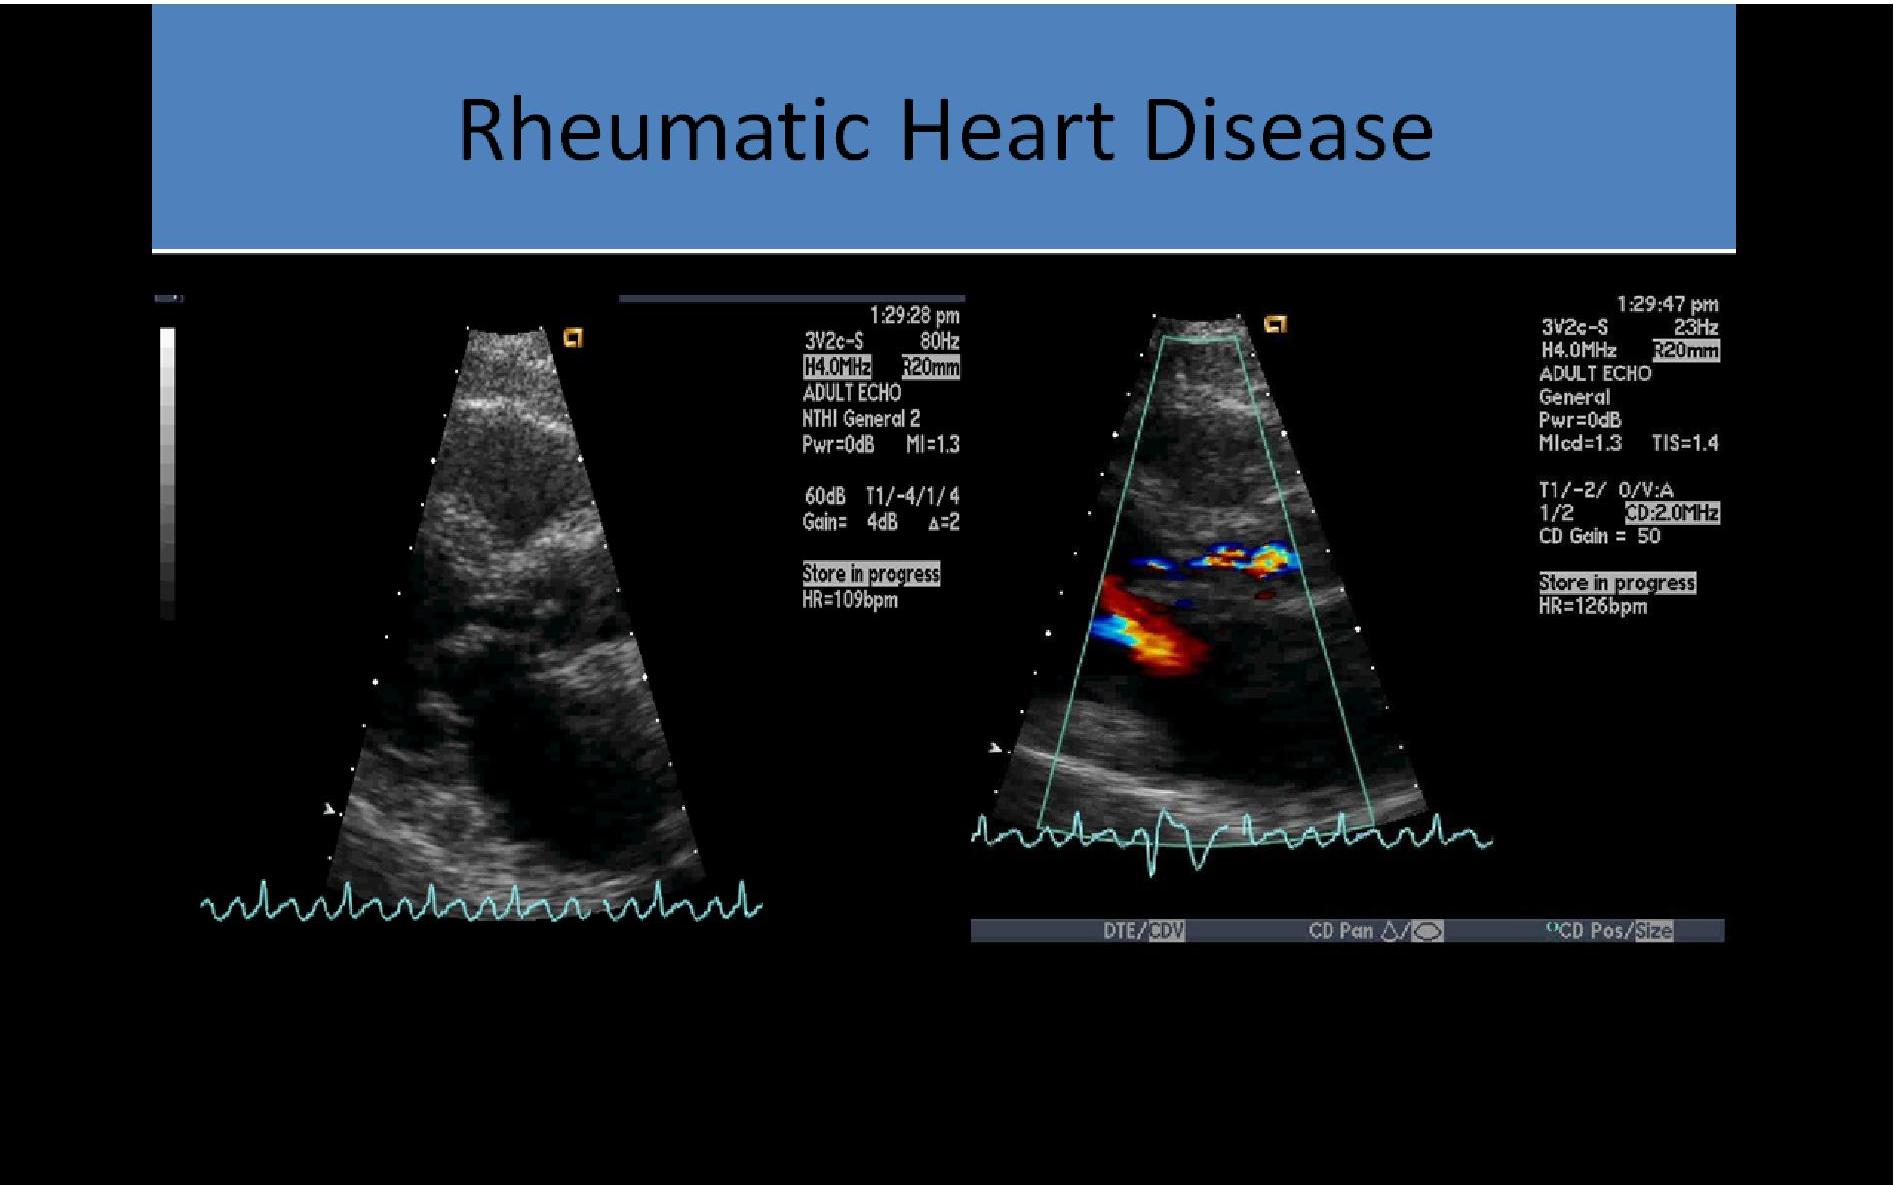

aortic stenosis disease rheumatic valve heart dimensionless abnormalities valvular ultrasound abnormal 2d valves congenital doppler leaflet velocity ai mr